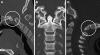

Background: The embryology of the bony craniovertebral junction (CVJ) is reviewed with the purpose of explaining the genesis and unusual configurations of the numerous congenital malformations in this region. Functionally, the bony CVJ can be divided into a central pillar consisting of the basiocciput and dental pivot and a two-tiered ring revolving round the central pivot, comprising the foramen magnum rim and occipital condyles above and the atlantal ring below. Embryologically, the central pillar and the surrounding rings descend from different primordia, and accordingly, developmental anomalies at the CVJ can also be segregated into those affecting the central pillar and those affecting the surrounding rings, respectively.

Discussion: A logical classification of this seemingly unwieldy group of malformations is thus possible based on their ontogenetic lineage, morbid anatomy, and clinical relevance. Representative examples of the main constituents of this classification scheme are given, and their surgical treatments are selectively discussed.